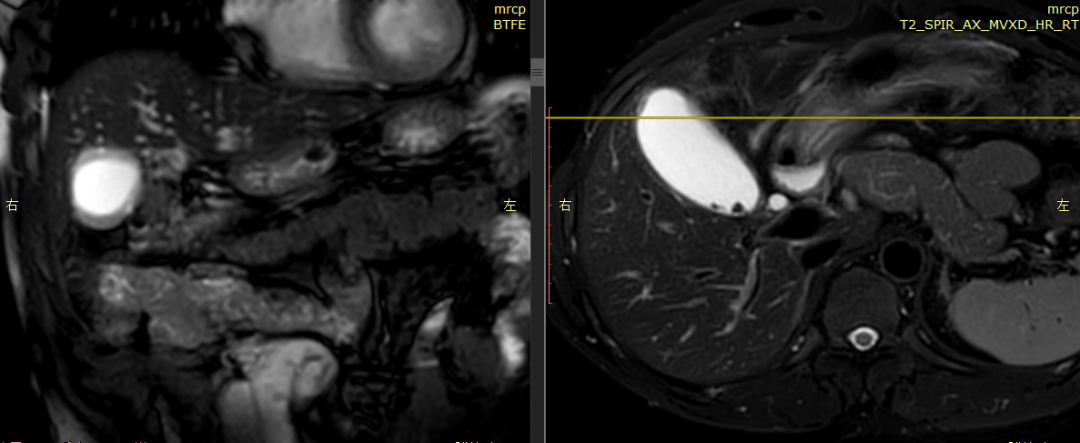

CASE 1